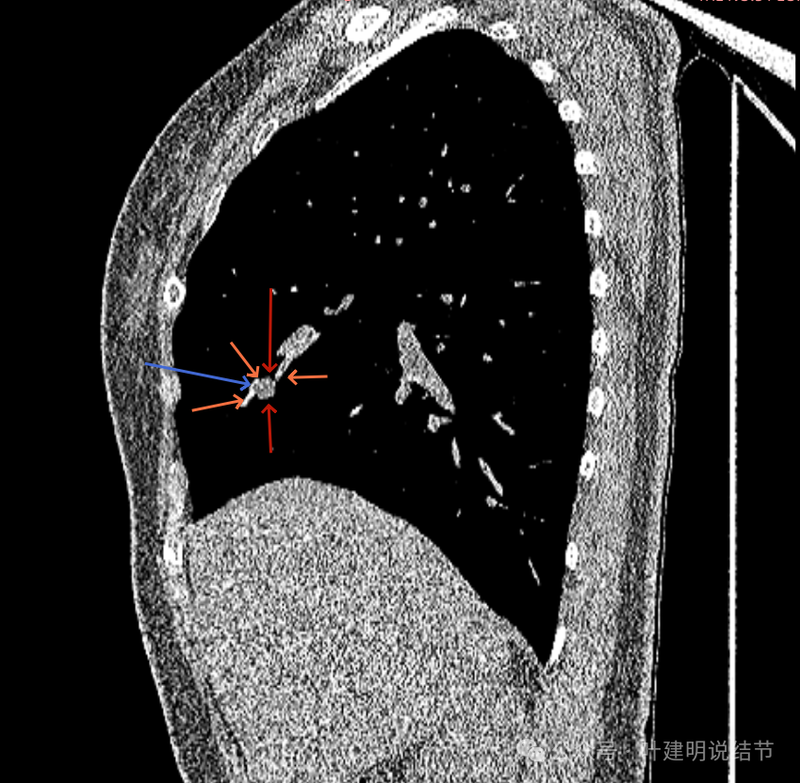

再看矢状位影像:

桔色的是血管,红色的是病灶,两者之间有间隙仍用天蓝色细线标注。

紧挨但仍有缝隙的。

血管贴着病灶,病灶表面略有毛糙之处。

血管有形成轻微血管弯征,两者紧贴。

两支血管夹着病灶,密度不同,有低密度间隙。

病灶与两侧血管关系均密切,明显觉得密度是不一样的,血管的密度略高,结节的略低。

病赤与血管在蓝色箭头处失去间隙,像是侵蚀血管壁,造成血管受侵犯破坏。病灶是软组织密度的,而且整体看有膨胀感。

病灶密度稍不均。表面不光滑。

病灶与边上血管间隙不清。

桔色箭头所示的血管受压稍有移位。

密度不同,关系密切。

边缘区域也是有膨胀感。

血管与病灶脱开后的样子。

边缘区也是基本上实性的。